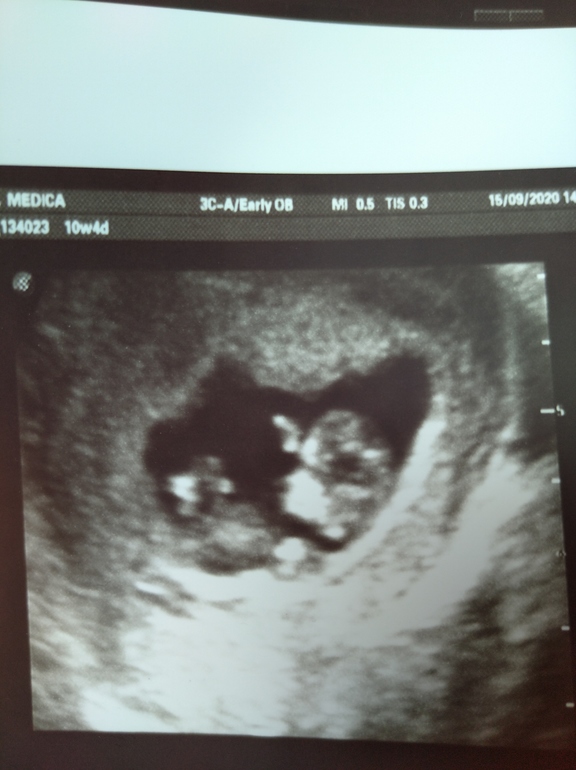

Ой, сегодня сходила на УЗИ внепланово. Живот пару дней просто адски болит. Посмотрела на монитор и поняла почему, там кошмарный гипертонус. Зато лялька в порядке, все хорошо. Уже даже носик увидели, так что скрининга я не боюсь)) Вся обкололась, свечи запихнула, таблетки выпила и лежу, жду когда полегчает Смотри какая прелесть